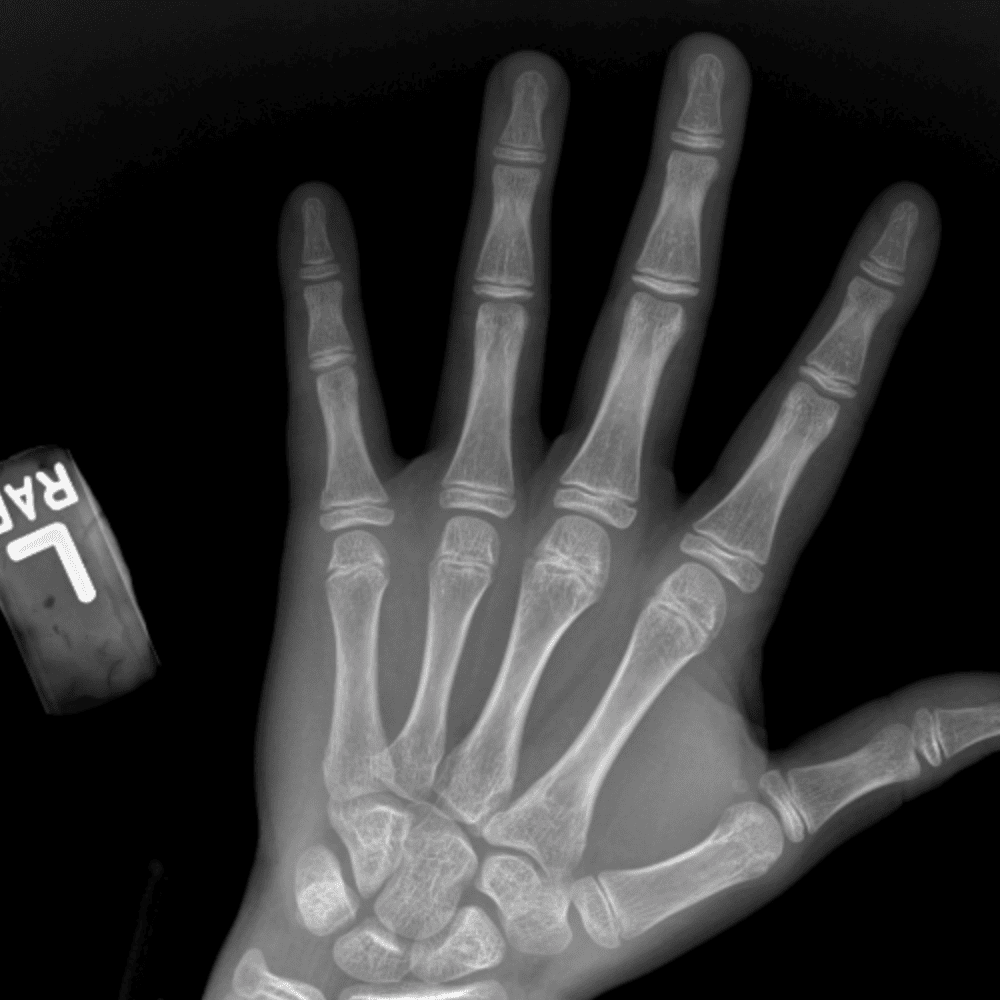

Simulates call by including subtle or difficult cases and some normals.

30 cases